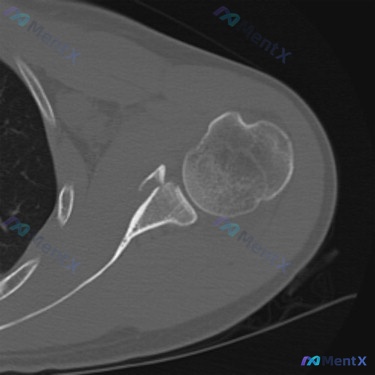

- 影像表现:CT轴位骨窗显示肩胛盂前下缘游离骨块,骨折线累及关节面,肱骨头对合关系基本正常(未见明显脱位)

- CT的“硬核”发现:肩胛盂前下缘关节内骨折、骨块分离——典型的骨性Bankart损伤,不是单纯的软组织Bankart

- 支持点:CT明确显示关节内骨折、骨块分离,符合前方不稳的经典损伤